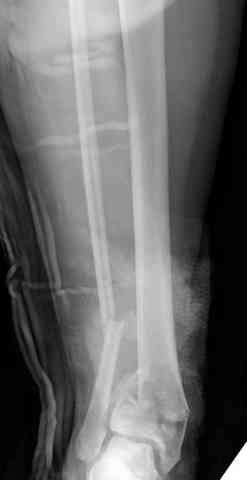

Дополнительные ренгенограммы после дистракции и

обязательная комьютерная томография дают возможности разузнать топографию расположения фрагментов, что немаловажно для планирования хирургического доступа.

По апексу фрагмента ориентируется при планировании

фиксации, также предоперационно определяется

направление фиксирующего материала: шурупа или спицы с упорной площадкой.

Первичная пластина или интрамедуллярный фиксатор на малоберцовую зависит от характера перелома, косые и многооскольчатые пластинами, а поперечных можно интрамедуллярными фиксаторами. Восстановленная длина малоберцовой служит ориентиром и помогает определению высоты большеберцовой во время восстановления.

Здесь выставлена пара случаев перелома пилона, оба

случая леченные этапным наружным фиксатором.